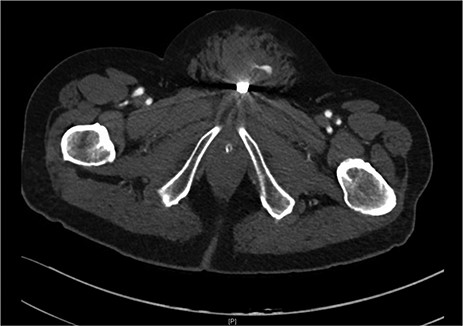

After discussion with urology, a 14Fr indwelling catheter was inserted, which drained yellow urine. A computed tomography (CT) mesenteric angiogram demonstrated penetrating injury to the suprapubic region with haematoma and two foci of arterial extravasation with radiological evidence of peritoneal breach, and the metallic foreign body in situ (Figs 2 and 3). Importantly, the tip of the knife appeared to end at the base of the penis at the expected confluence of the dorsal vein.

Suprapubic stab wound: coronal section: CT mesenteric angiogram showing mons pubis haematoma with active arterial extravasation.